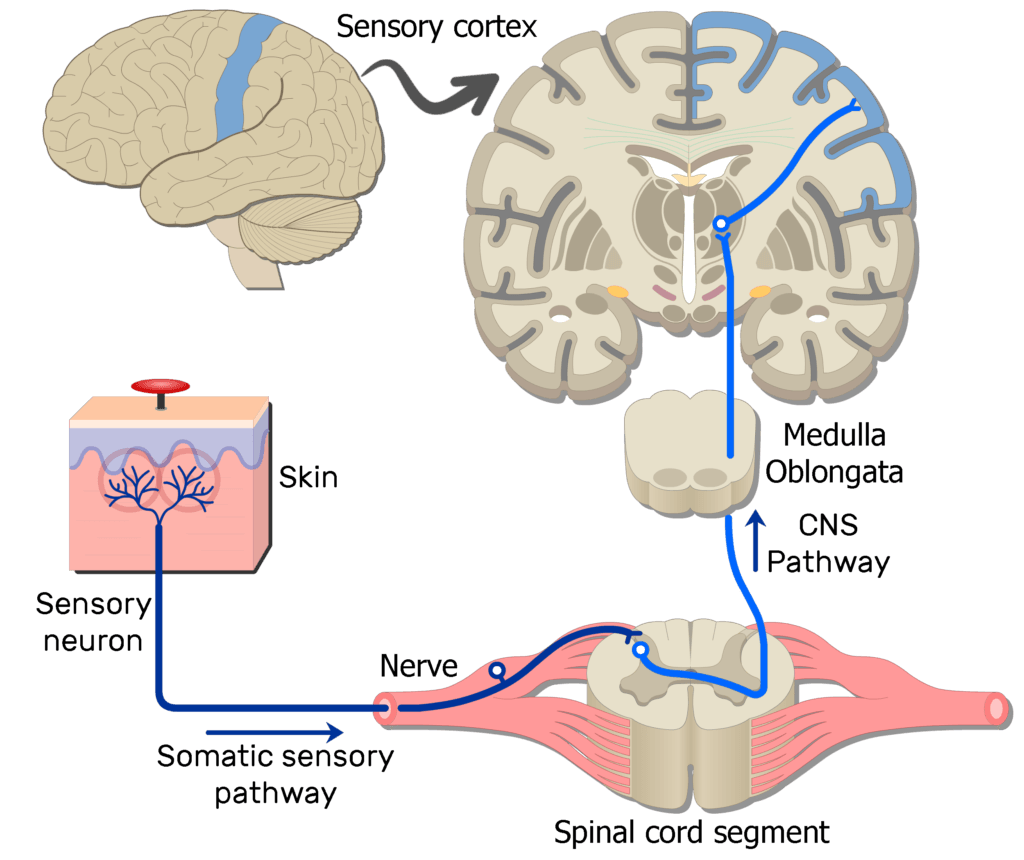

Pain perception relies on a sophisticated network of nerves called the **pain neuroaxis**, which includes:

– Peripheral nerves (outside the brain and spinal cord)

– Central neurons (in the brain, brainstem, and spinal cord)

When you feel pain, these neurons send signals to the brain, where multiple regions interpret them. While acute pain serves as a protective warning system, chronic pain often persists without purpose, indicating a dysfunction in pain processing.